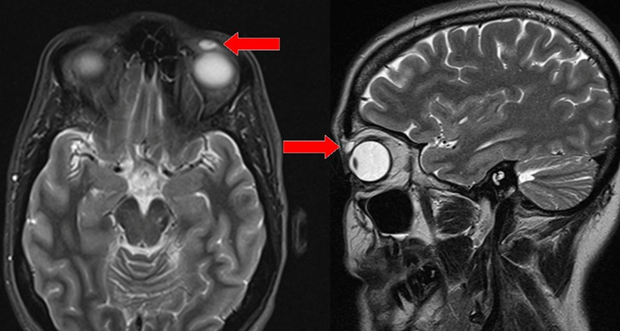

В прошлом году 42-летняя британка обратилась к врачу с необычной жалобой. На ее правом веке вздулся бугорок, который почти закрывал глаз. Женщина полгода старалась не обращать на него внимания, но тот увеличился до таких размеров, что дольше игнорировать было невозможно. Доктор осмотрел ее и не нашел никаких признаков травмы. Он провел МРТ-сканирование и заметил небольшое образование над глазом, всего шесть миллиметров. Пациентке сообщили, что придется идти на операцию, чтобы понять природу странного комка. Она согласилась.

Когда припухлость надрезали, внутри обнаружили жесткую линзу. Для ее удаления потребовалось все мастерство хирургов, так как та оказалась очень хрупкой, и одно неверное движение могло расколоть ее на множество маленьких осколков, которые пришлось бы искать и извлекать по отдельности, но все закончилось благополучно.

Узнав о результатах операции, женщина очень удивилась: она давно отказалась от линз и не знает, как та могла попасть ей в глаз. Загадку разрешила мать пациентки, которая вспомнила случай из дества, произошедший 28 лет назад. Ее 14-летняя дочь тогда играла в бадминтон. Волан угодил девочке в глаз, и линза пропала. Родители решили, что та выпала, но она, видимо, сместилась и застряла в веке — на 28 лет.